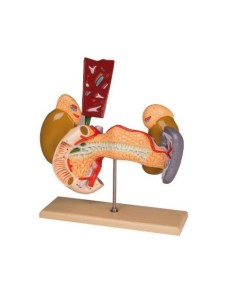

Modello anatomico di orecchio di bambino ingrandito 1,5 volte - Erler Zimmer E25